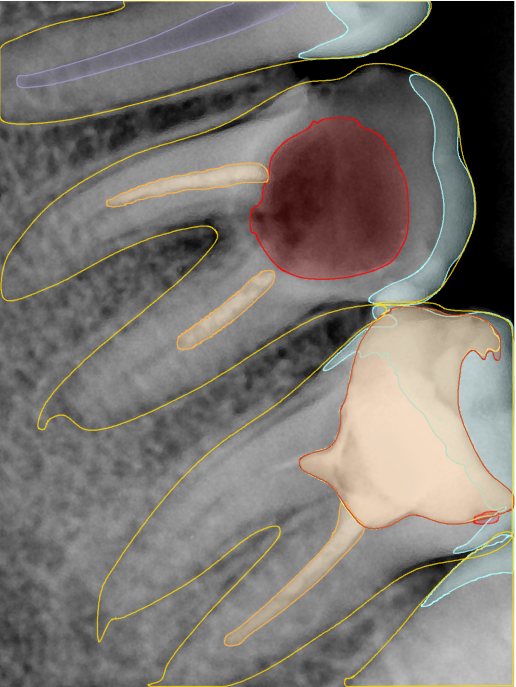

CR/DR 牙齿分割阶段记录

当前进展

- 完成了 CR/DR 牙齿相关分割训练

- 当前结果已经达到阶段预期,但仍有细节问题需要继续处理

相关测试

遇到的问题

- 训练过程中出现过 mask 下移问题

- 部分结果会出现 box 填充异常

- mask 边缘仍然有比较明显的锯齿感

第二版算法问题测试